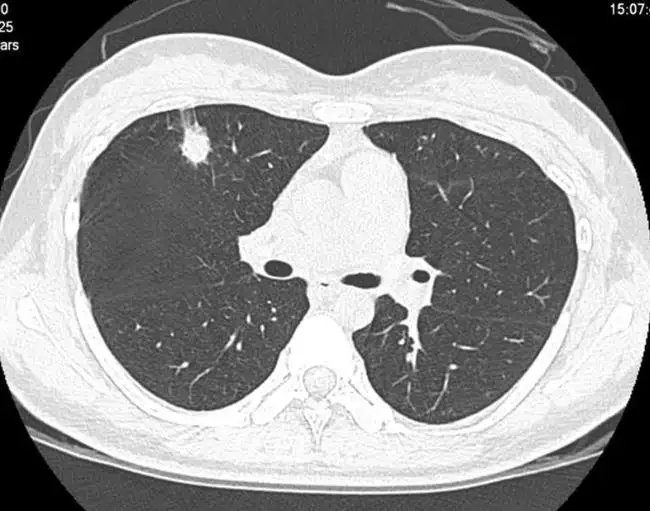

大家都会非常关心,想咨询一下肺结节究竟要不要做手术,应该怎么处理,我是不是应该到国内有知名的专家的那个地方去看呢?其实肺结节最佳的处理方式就是一个随访,那么我们如何进行一个随访呢?我们在第一次发现这个肺结节的时候,就判定这个肺结节有没有风险,大家经常会私信,或者是在视频下面留言,有多大多大的一个结节,是不是恶性的,要不要做手术等等,需要做手术或者是不是恶性的话,我就要去看他的细节,谈到细节的话,大家平时拿到的这样一个胶片,几毫米的结节我们是看不清楚的,我们需要在电脑上进行一个放大。

我们放大了要看什么呢?看这个结节的边缘,他有没有毛刺,有没有分页等等这些高风险的因素,比如说胸膜牵拉呀等等,如果合并了这些高风险因素,它又是大于六到八毫米的,我们就成为他有风险了,所以你刚给我提出的这个九毫米的结节,要不要做手术,我是没办法回答,如果是第一次发现的话,我都会建议患者进行随访观察,曾经也有一些患者,他拿着第一次发现呢,他要求我给他手术切除,我就会综合来判定,如果他风险并不高的话,我是不会去给患者做一个切除的。有部分患者他在随访观察的过程中,他那个结节它是会消失或者变小的,在这种情况下,如果他选择了手术,尤其是一个良性的结节,如果选择了手术,对患者还是一个比较大的一个创伤,我们再试一个微创手术,对患者都是有影响的,所以我的观点是发现了,结节,我还是建议随访,我们要尽量避免手术,而不是想方设法的去把它切除。